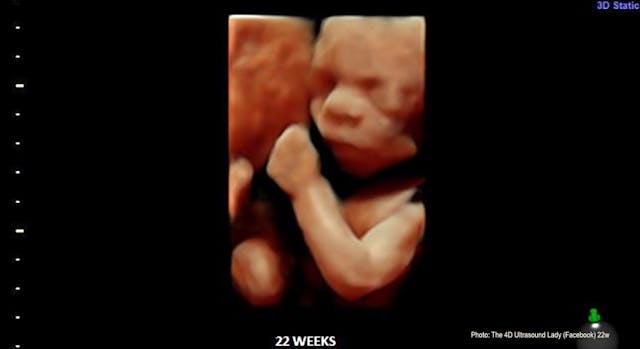

More babies born at 22 weeks are surviving, but it’s still legal to kill them

A 2025 study published by the Journal of the American Medical Association (JAMA) has revealed that both active medical treatment and the survival rate of babies born as early as 22 weeks are increasing.

A new study found that active treatment and survival rates for babies born at 22 weeks and 23 weeks are increasing.

Between 2014 and 2023, survival among 22-weekers who received active treatment rose from 25.7% to 41%.

Rates of survival rose from 7.4% to 32% for babies born at 22 weeks who did not receive active treatment.

The study analyzed the survival rates of nearly 58,918 premature infants. According to MedPage Today, both active treatment and survival rates among 22-week premature infants increased. Active treatment rose from 28.8% to 78.6% and survival rates for those infants increased from 25.7% to 41%. Active treatment as well as survival rates for infants with active treatment also increased for those born at 23 weeks. Active treatment rose from 87.4% to 94.7% and survival rates rose from 53.8% to 57.9%.